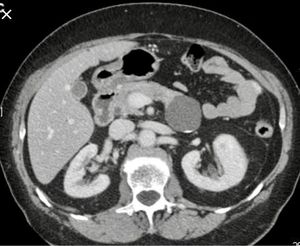

If it isn't pancreatic cyst then idk but definitely not hydronephrosis. Anyone thinking hydroneph should prolly quit medicine

pancreatic tail cyst

Pancreatic cyst

Pancreatic cyst.

It’s pancreatic tail cyst guys, thanks for your patience